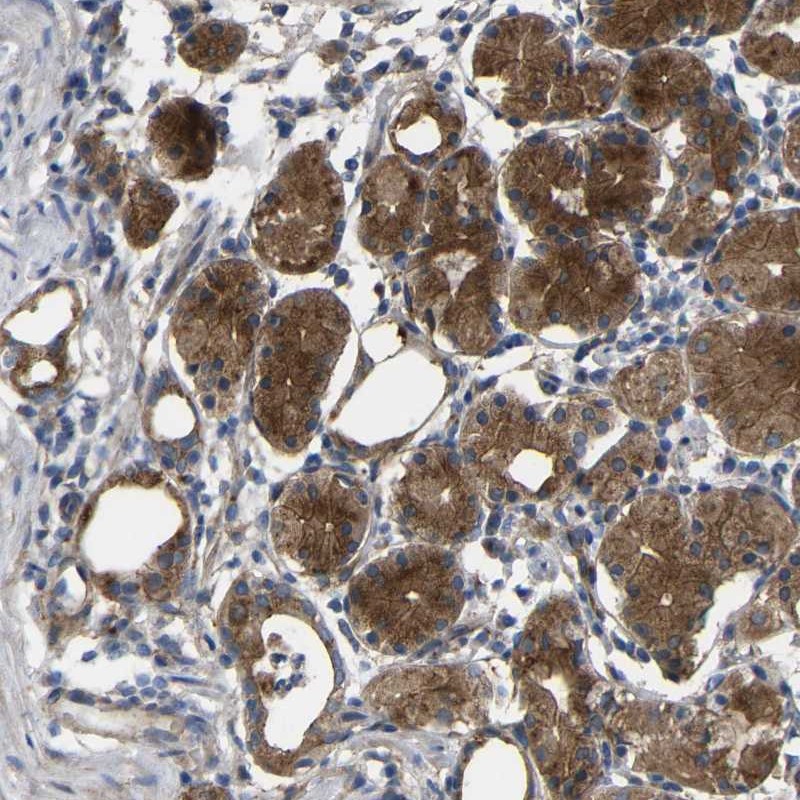

Immunohistochemical staining of human stomach shows strong cytoplasmic positivity in glandular cells.